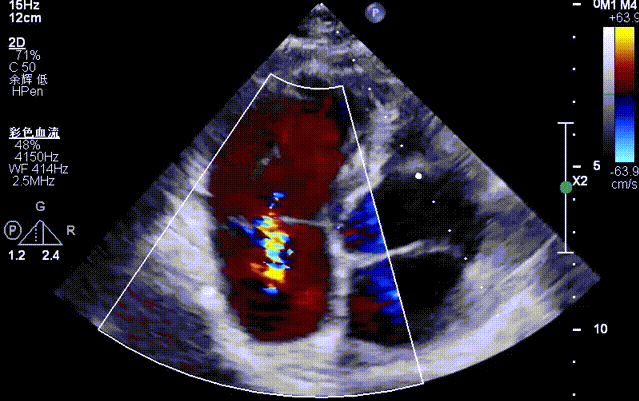

Tricuspid Valve Annuloplasty Stage:Subsequently, via the right internal jugular vein approach, the K-clip® transcatheter tricuspid valve annuloplasty system was delivered to the right atrium. With the assistance of three-dimensional ultrasound stereoscopic views, a 12T clip was successfully implanted at the posteroseptal commissural annulus of the tricuspid valve, and a 14T clip at the anteroposterior commissural annulus, achieving effective constriction of the dilated annulus. Immediate postoperative assessment demonstrated that tricuspid regurgitation was improved from severe (4+) to mild (1+) instantaneously.

1.Intraoperative baseline assessment of regurgitation severity

Preoperative regurgitation (severe)

Postoperative regurgitation (trivial)

Surgical Outcome: Severe tricuspid regurgitation (4+) was reduced to mild tricuspid regurgitation (1+).